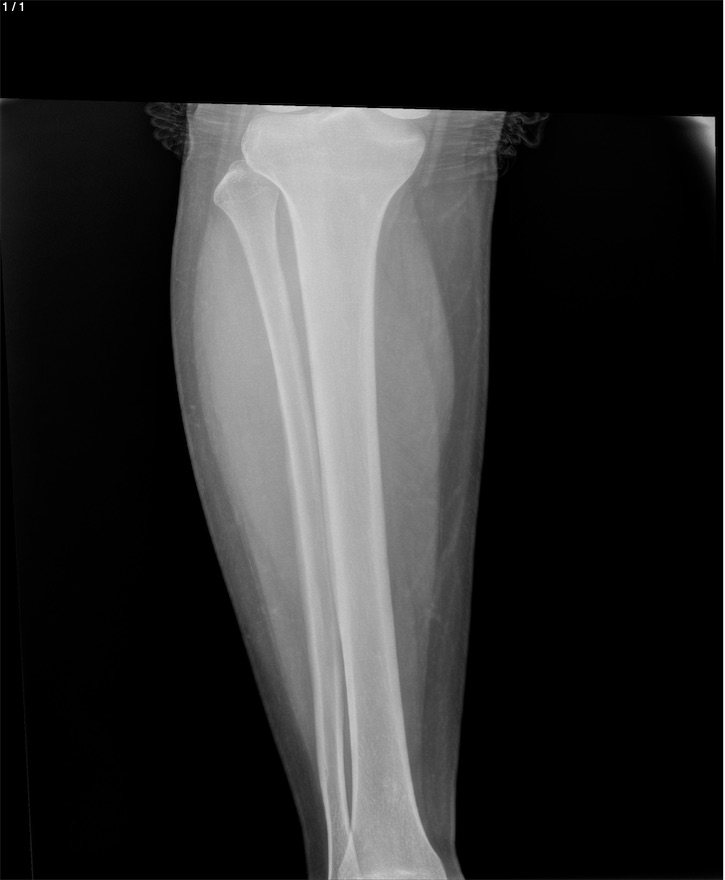

Angel Eduardo Lopez - Unnamed